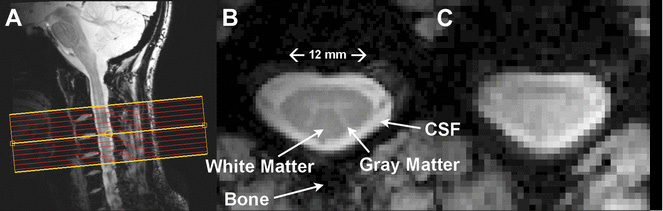

Researchers have noninvasively measured neural signaling in the spinal cords of healthy human volunteers. Above: Resting state spinal cord fMRI at 7 Tesla. (A) Mid-sagittal slice from a healthy volunteer showing the complete cervical cord and typical axial slice placement for this resting state study. In all subjects the imaging stack was centered on the C3/C4 junction, providing full coverage of C3 and C4 and partial coverage of C2 and C5. (B) T2*-weighted anatomical image at C4 acquired with 0.6 × 0.6 × 4 mm3 voxels and interpolated to 0.31 × 0.31 × 4 mm3. Excellent contrast permits visualization of the characteristic butterfly-shaped gray matter column. (C) A single T2*-weighted functional image of this axial slice (acquired with 0.91 × 0.91 × 4 mm3 voxels). Functional images are high quality with minimal geometric distortions and T2* blurring and permit adequate spatial delineation between white matter and cerebrospinal fluid. Images courtesy eLifesciences.